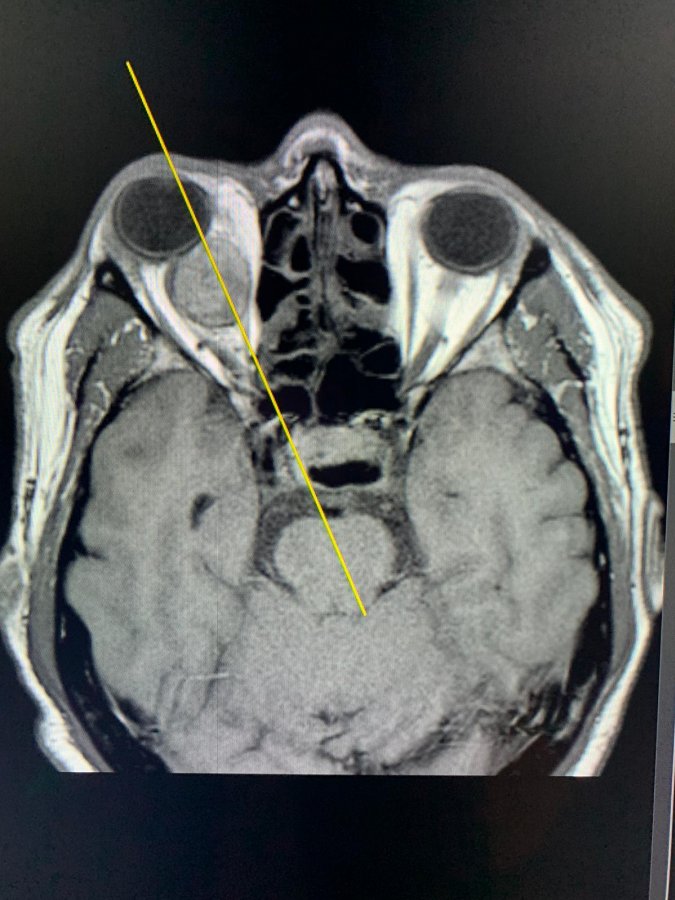

Była to niezwykle skomplikowaną operacja usunięcia olbrzymiego guza przyśrodkowej części oczodołu.

- Podczas tej operacji zastosowaliśmy dwie techniki operacyjne: „atakowaliśmy” endoskopowo guz od strony nosa, a pod powiększeniem ezgzoskopowym, z dojścia od przodu przez spojówkę oka, odpreparowaliśmy go od niezwykle delikatnych nerwów i naczyń oczodołu - tłumaczy dr hab. Tomasz Łysoń, z Kliniki Neurochirurgii. - Z całą pewnością jest to pierwsza tego typu operacja w Polsce, a zapewne również i na świecie. Operując oczodół pod mikroskopem, nie moglibyśmy wprowadzić do nosa endoskopu, gdyż te dwa urządzeni po prostu by się w tym małym polu operacyjnym nie zmieściły.